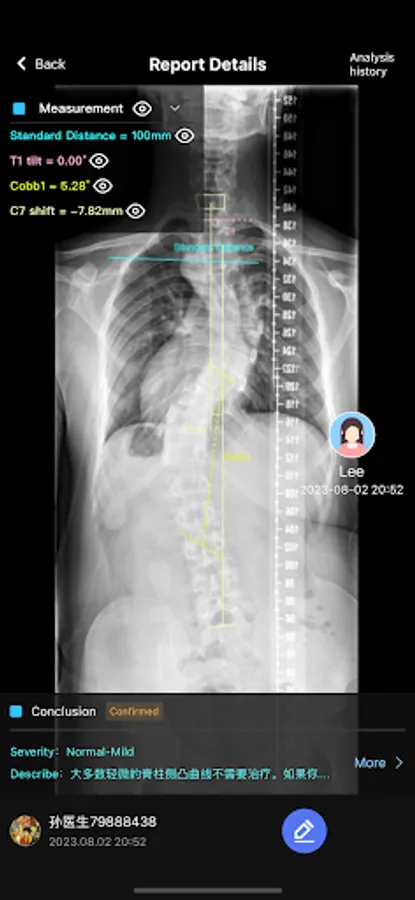

2. AI intelligent analysis of the condition, doctors can edit and review diagnosis and treatment reports;

5. Upload patient images, support X-ray, naked back, side back, etc.;